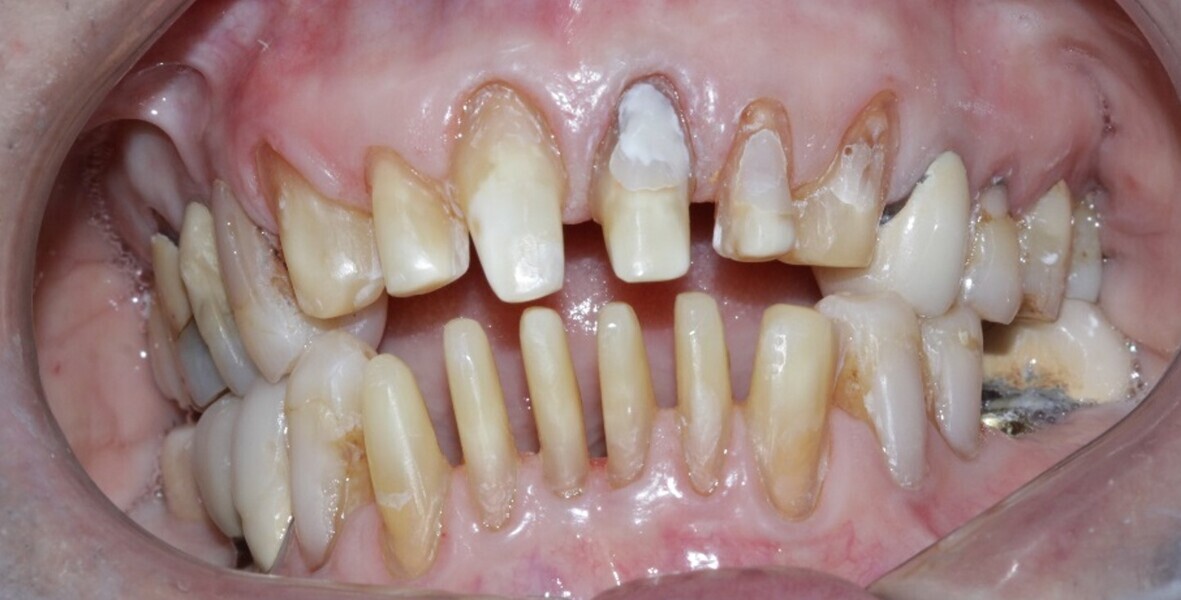

Figure 1 Close up smile before treatment